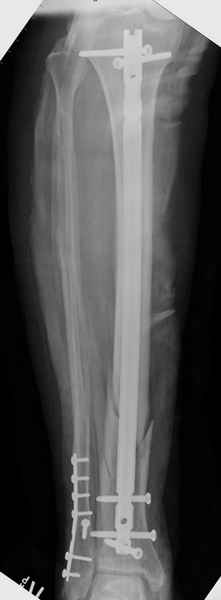

Здесь мы использовали новый Synthes Nail с дополнительными дырками, в проксимальной части 4: по две косых и поперечные (один стандартный а другой динамический), в дистальной части две поперечные, прямая и косая. Вес больного более 120 кг, нагрузку начнем через месяц.

Получилось красиво, поздравляю. Вверху можно было ограничиться одним винтом во фронтальное статическое отверстие, зачем два 45-градусных?

При такий спирали задний край tibia может быть сломан - нет ли этого в данном случае? На всякий случай можно было ввести 1-2 винта 4,5 мм спереди назад мимо гвоздя. Хотя самый дистальный блокирующий винт, возможно, зацепил этот отломок. А какой тут диаметр гвоздя и locking винтов?

DK> косая. Вес больного более 120 кг, нагрузку начнем через месяц.

Если там и правда сломан задний край, то лучше с нагрузкой подождать, даже будь больной полегче.